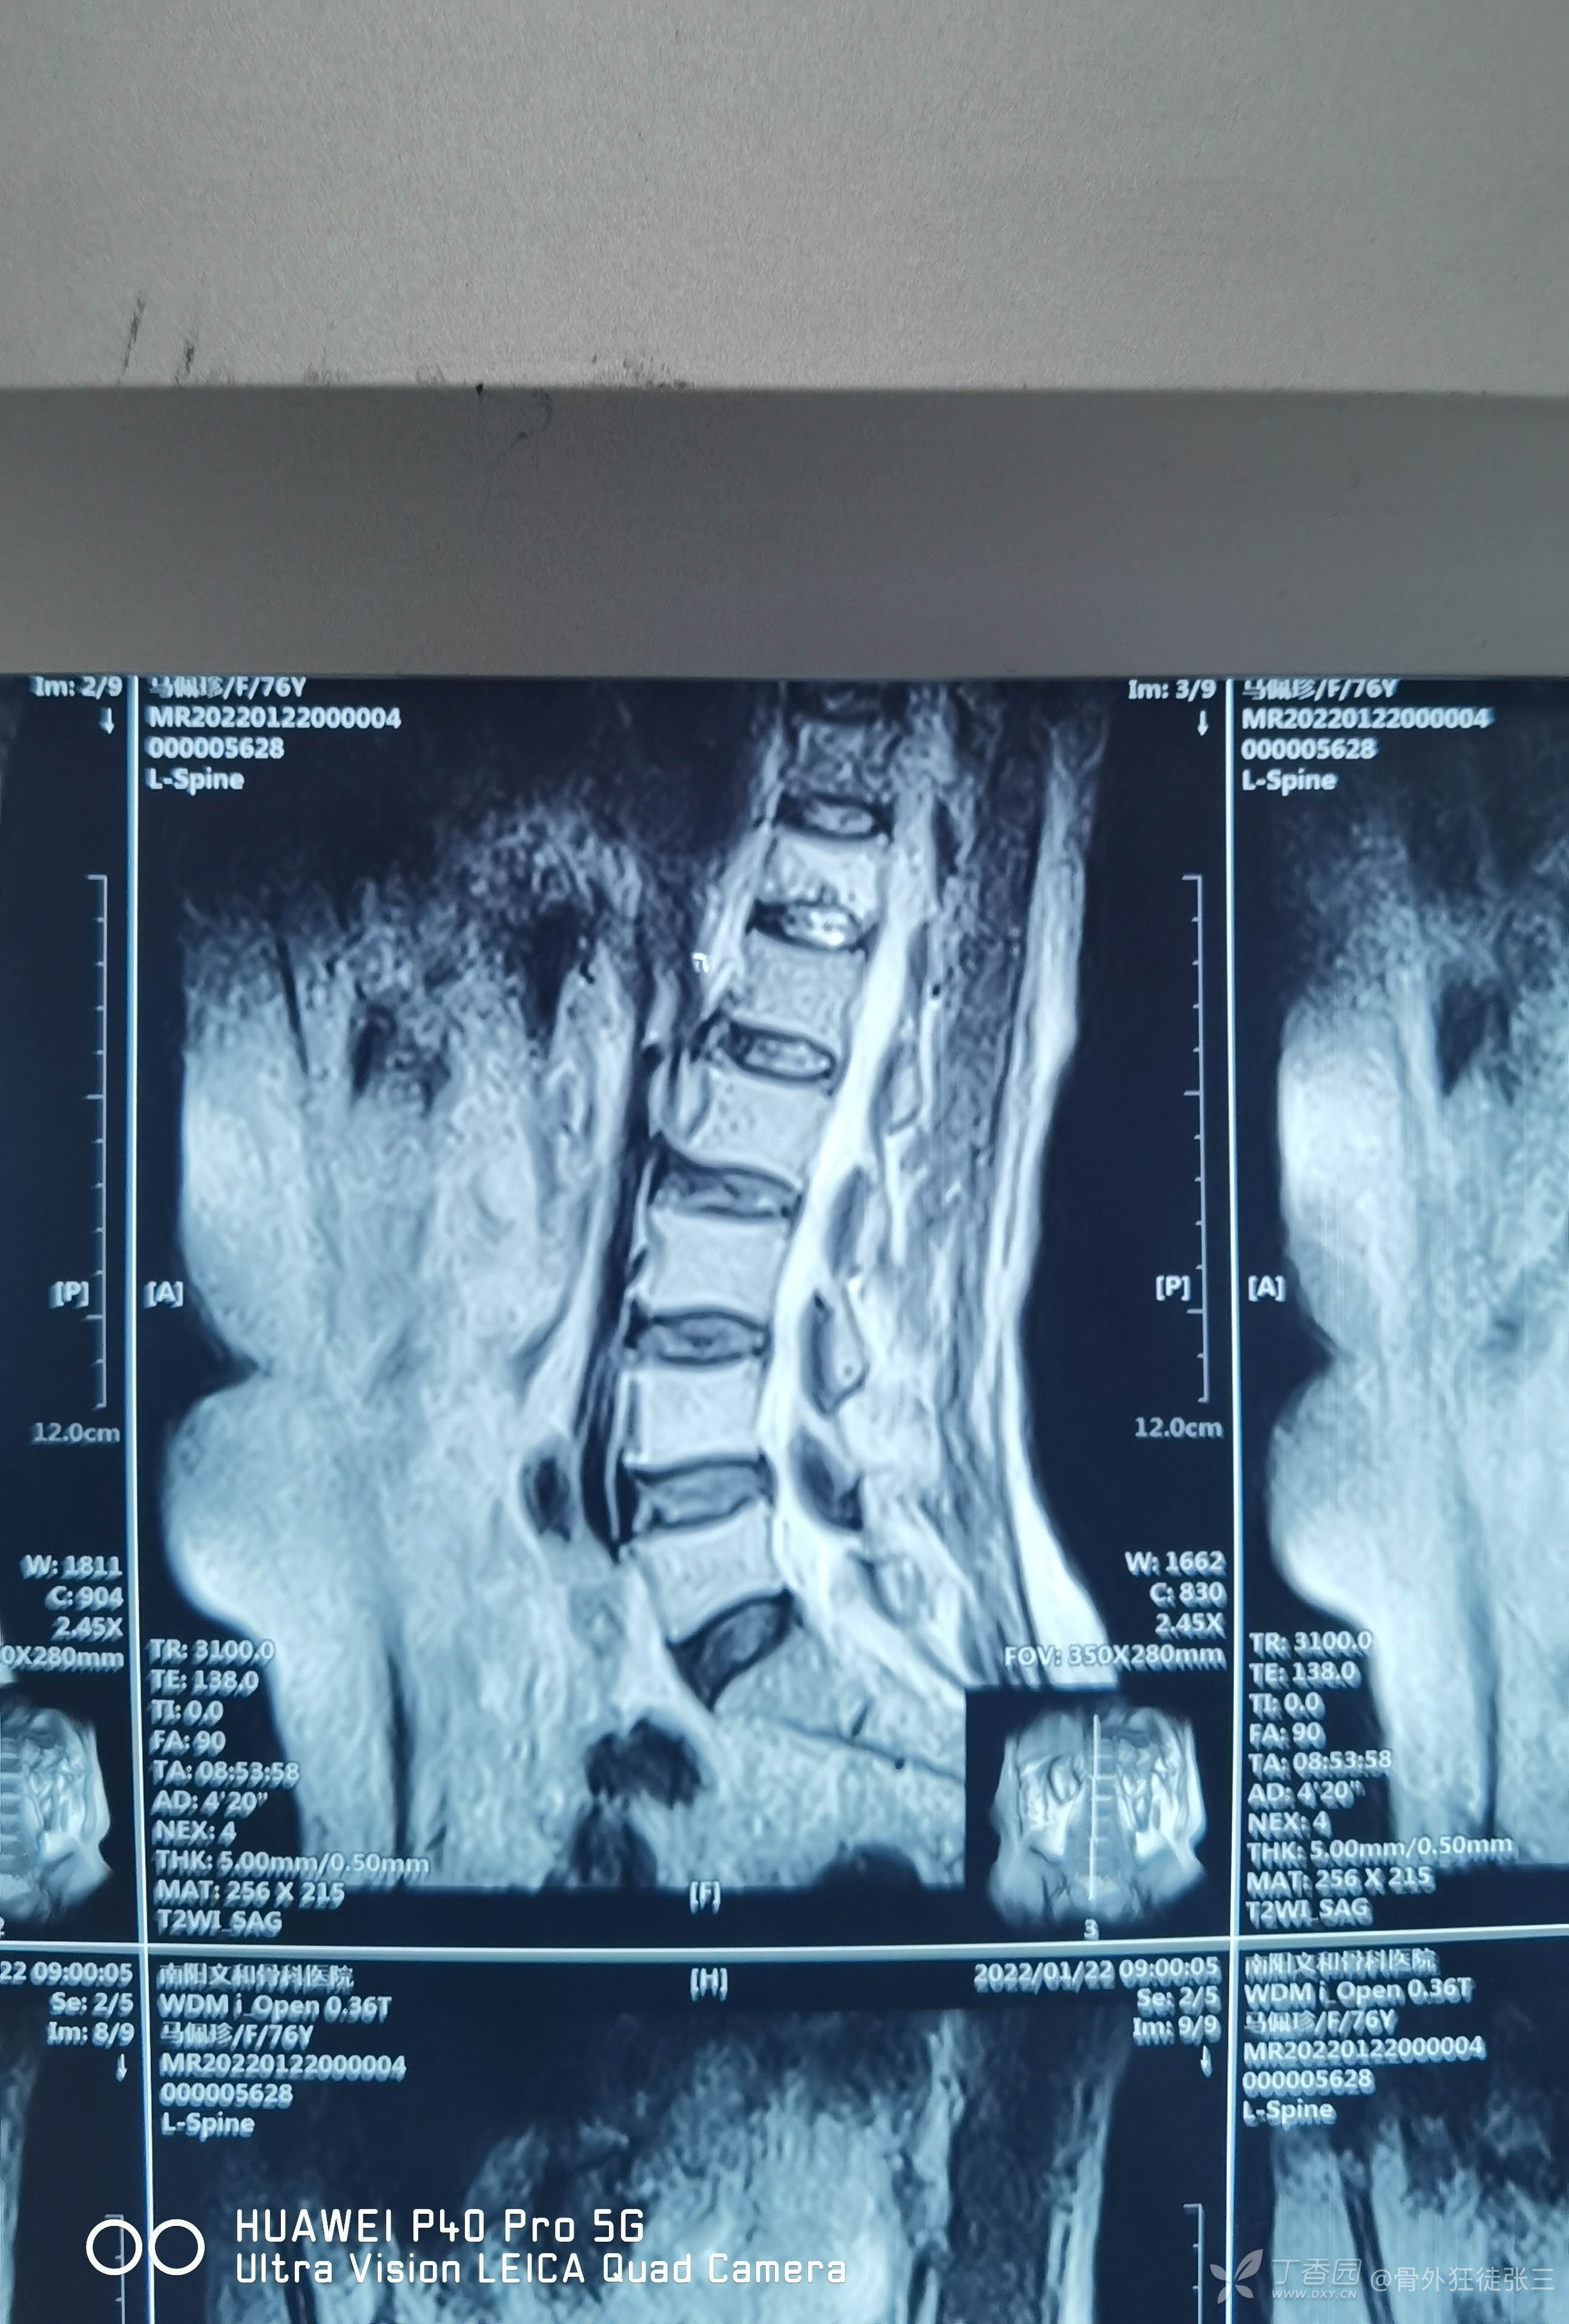

辅助检查X线,CT,核磁示:

胸12椎体压缩骨折

术前讨论后行经皮穿刺椎体成形术。

术前定位